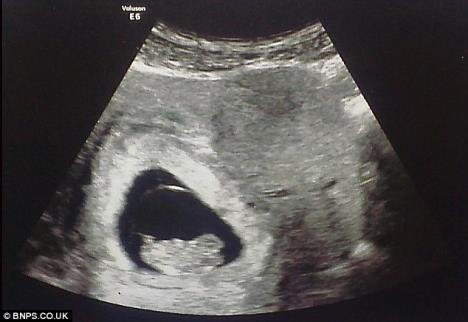

Slika sa ultrazvuka

USLIKAN: Anđeo čuvar bdi nad nerođenom bebom

LONDON - Buduća mama En Klulou ostala je zatečena kada je na slici ultrazvuka svoje nerođene bebe videla lice muškarca nalik vanzemaljskom?!

Lik nalik nekom duhu zurio je u nju sa crno-bele fotografije. Džinovska ljudska, ali izdužena glava delovala je zastrašujuće međutim trudnica se nije uplašila - ubeđena je da je to anđeo čuvar njenog nerođenog deteta.

En ima i starijeg sina od 10 godina, a treba da se porodi u avgustu.